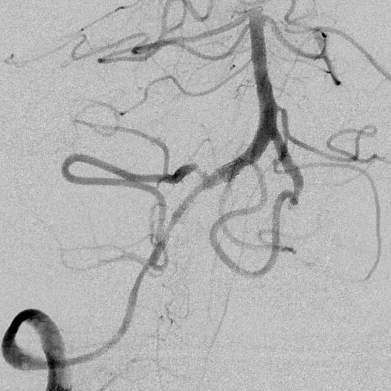

相逢就是缘,有求必全力以赴。立即进行全面评估,CTA和MRI发现颅内多发脑梗塞,脑干为重,双侧椎动脉颅内段基本看不到了,而进一步的DSA造影更为糟糕,左侧椎动脉的颅内颅外段直接全程完全闭塞,右侧颅外剩下一个小尾巴在血液中摇摇欲坠……,诺大的后循环仅仅靠纤细的后交通动脉从前循环借点血液过来,勉强续命,仅仅靠这点前循环的救急,可谓“杯水车薪”,不是“长久之计”,于是决定开通右侧闭塞的椎动脉(颅内+颅外,主要集中在V3+V4段)。

微导管继续超过去,轻轻造影,开通的路径隐约返流闪现,立即改变策略,逆向铺路,开通成功。

术后查房,患者头晕消失,双侧听力基本恢复,整个手术时间历时7个小时,过程是艰难的,结果是欣慰的~~~